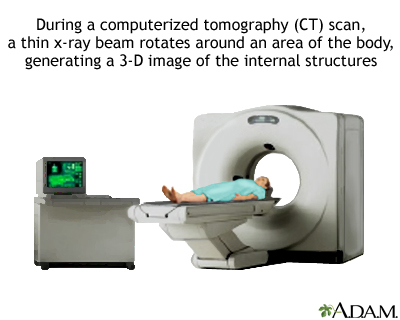

An abdominal CT scan is an imaging test that uses x-rays to create cross-sectional pictures of the belly area. CT stands for computed tomography.

You will lie on a narrow table that slides into the center of the CT scanner. Most often, you will lie on your back with your arms raised above your head.

Once you are inside the scanner, the machine's x-ray beam rotates around you. Modern spiral scanners can perform the exam without stopping. There is very little noise.

A computer creates separate images of the belly area. These are called slices. These images can be stored, viewed on a monitor, printed on film or saved to a disk. Three-dimensional models of the belly area can be made by stacking the slices together.

You must be still during the exam, because movement causes blurred images. You may be told to hold your breath for short periods of time.

The scan should take less than 30 minutes.